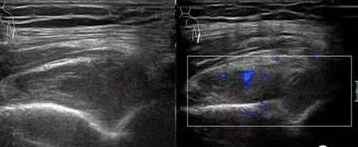

风湿免疫性疾病在肌骨关节方面的主要表现为滑膜炎、滑膜增生、肌腱及腱鞘的炎性改变以及附着端炎、骨质的侵蚀破坏等。通过灰阶超声及能量多普勒来评估关节的具体结构。

超声探测关节软骨面的“双轨征”改变成为痛风性关节炎的特异性表现,为痛风的诊断提供了客观的诊断依据。